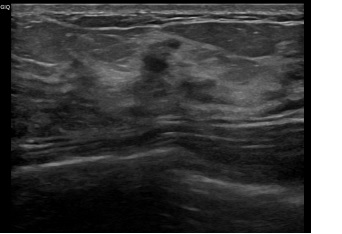

상기환자는 좌측유방 통증있어 내원하신 40대 중반

여성분으로 의심스러운 좌측혹 조직검사 시행해 소엽제자리암 진단되었습니다.